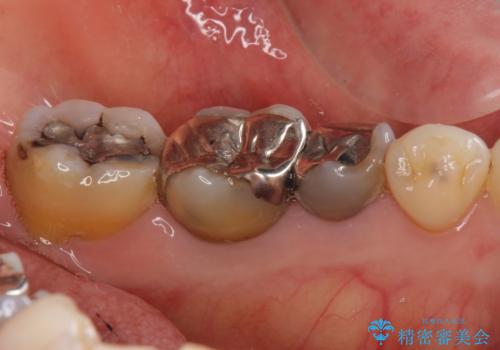

- 左下の銀歯を白くしたいと来院。

左下5番は根管治療のやりなおし、左下6番は上物(クラウン)のやり替えのみを行いました。

左下7番はアマルガムが入っていたため、ご希望によりセラミックインレーで治療を行っています。

アマルガムは水銀を含むため、やり替えの希望をされる方が多くなっています。